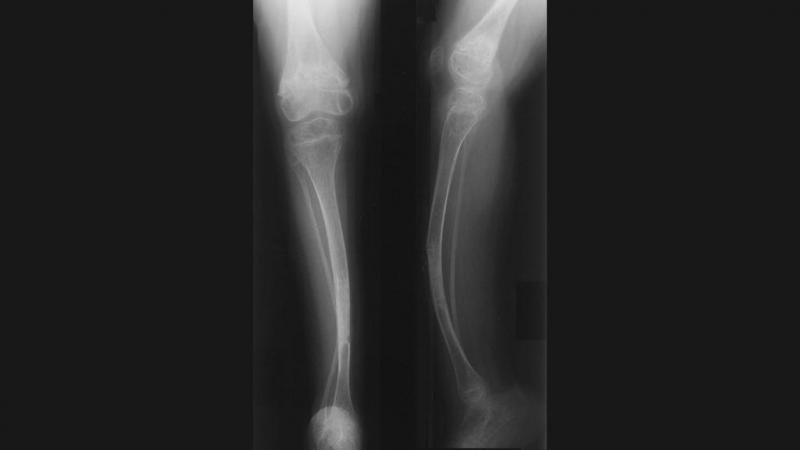

La osteogénesis imperfecta es un trastorno genético en el cual los huesos se fracturan con facilidad, algunas veces sin un motivo aparente. También puede causar músculos débiles, dientes quebradizos, una columna desviada y pérdida del sentido del oído. Según información del Ministerio de Salud (Minsa), solo en enero del 2022 se reportaron 19 casos de pacientes con este trastorno.

La osteogénesis imperfecta es causada por uno o varios genes que no funcionan bien. Esto afecta la manera en que el cuerpo produce colágeno, una proteína que ayuda a fortalecer los huesos. Puede variar desde leve hasta severa y los síntomas varían de una persona a otra. Un individuo puede tener apenas algunas fracturas o alcanzar varios cientos de fracturas en toda la vida.

No existe una prueba específica para la Osteogénesis imperfecta. Para su diagnóstico se puede usar la historia clínica y familiar, un examen físico y test de imágenes. También se podría hacer un examen de colágeno (de la piel) o genético (de sangre).